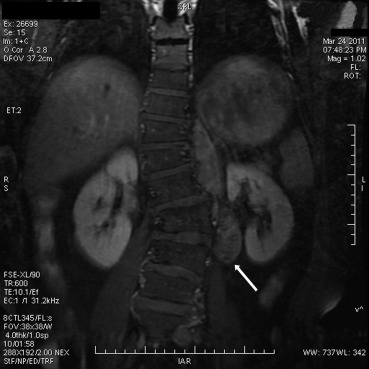

A 44-year-old male presented with intermittent pain in the left hypochondrium for twenty days. He had no significant past medical history. Magnetic resonance imaging revealed a left paravertebral soft-tissue mass of 9.0 cm in maximum diameter at the T11–L3 levels. The lesion was iso- and hypointense on T1-weighted images, heterogeneously iso- and hyperintense on T2-weighted images, where a higher cord-like signal intensity was present; in addition, it showed heterogeneously avid enhancement following the administration of the contrast agent (Fig. 1). He underwent a tumorectomy via the left posterolateral approach. Intraoperatively, a retroperitoneal mass was found at the left side of the vertebral column spanning from T11 to L3. The well-defined tumor was closely adjacent to the vertebrae and displayed no bone erosion. The patients postoperative course was uneventful. No additional treatment was administered. He was well and without evidence of disease at 2 years' follow-up.

Figure 1.

Magnetic resonance imaging reveals a left paravertebral soft-tissue mass, which is enhanced with an injection of contrast medium at the T11–L3 levels (arrow).